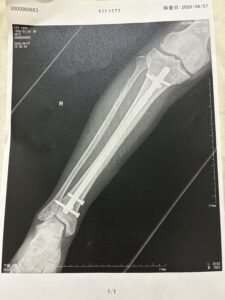

もう入院して20日ほど経ちました。

今は午前、午後とリハビリをして治療に励んでます。